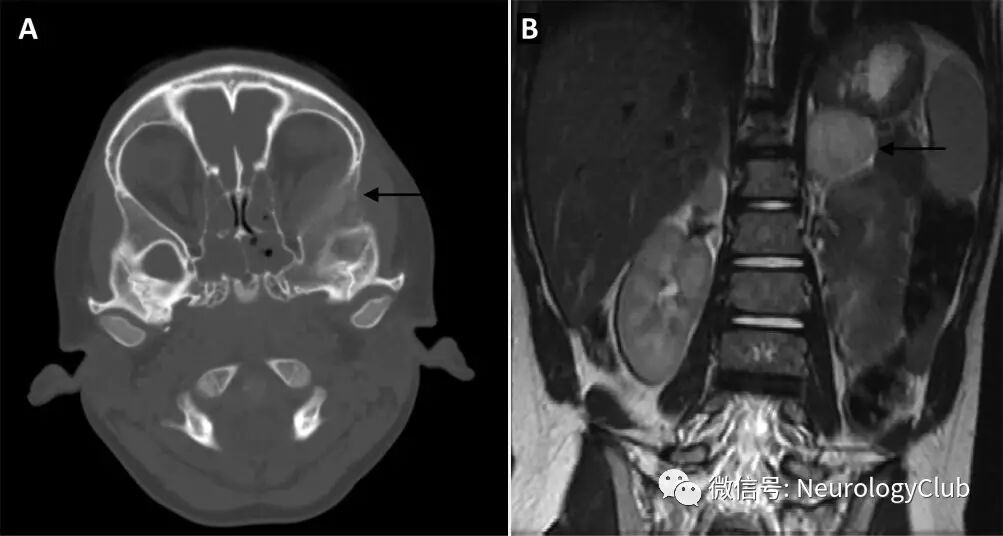

5岁男孩,表现为左侧眼球突出和眼窝疼痛1周,既往无用药和手术史。查体可见左侧眼球突出,无视野缺损和其他神经系统异常。血常规,电解质和炎症标志物正常。头颅CT可见眼眶内占位性病变。

(图1:横断面和矢状位头颅CT平扫)

典型的CT或MRI特征为源于眶壁的肌锥外软组织肿块。如本例患者,肿瘤可局部侵袭深入颞下窝结构或颅内,伴眶顶和眶壁骨性破坏以及骨针形成。